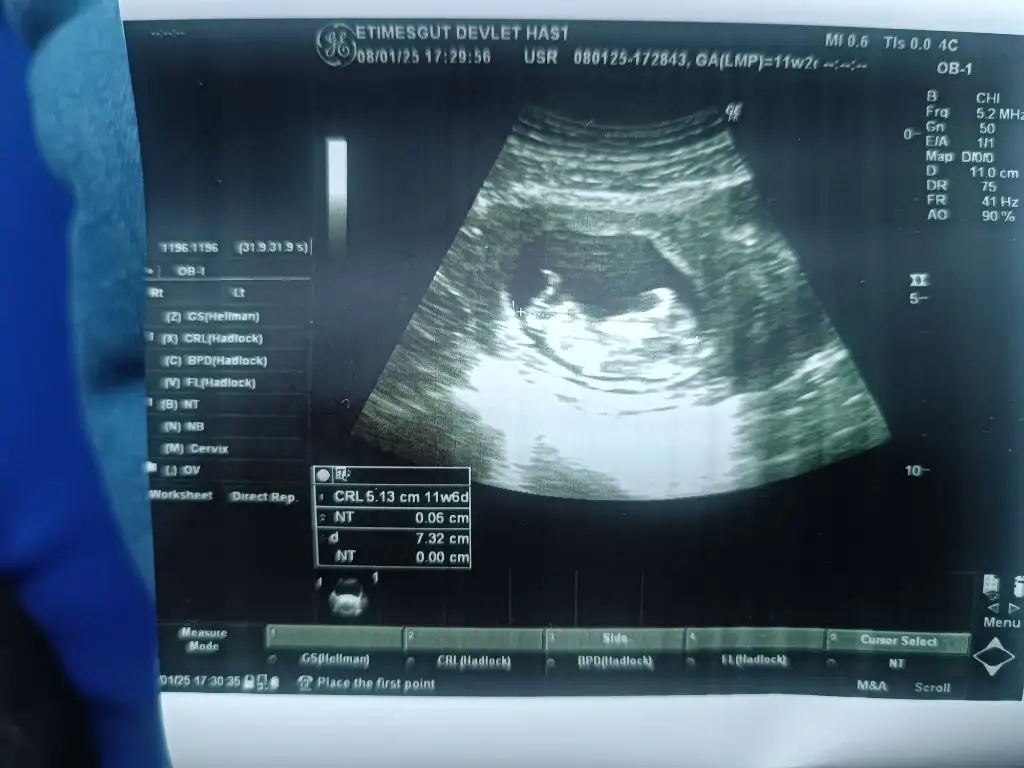

Şu an itibariyle 12+4 teyiz. Fetal yaptırmadık dün ikili teste girdim. Ense kalınlığı 0,95 çıktı burun ve alın kemikleri de mevcut. Kol ve bacaklarını yukarıya doğru uzatmış uyuyordu bizimki. O yüzden bacak arasını görmek zor olmadı. Doktor birkaç kez gösterip bacak arası boş ama şimdilik kız da erkek de diyemem dedi (ben kız isteyip hissediyorum başından beri).

Yaa duruşa bak maşallah bencede erkek gibi heybetli duruşu var Allah nazardan saklasınİyi haberlerle geldim kızlar bendeÇok şükür bebek iyiymiş içeride. Her şey yolundaymış Ense kalınlığı, burun kemiği her şey iyi çıktı. Cinsiyeti en erken 2 hafta sonra belli olurmuş. Var mı içine doğan cinsiyet konusunda tahmini olan Baksanıza içeride kara kara düşünüyor sanki Eki Görüntüle 3533578